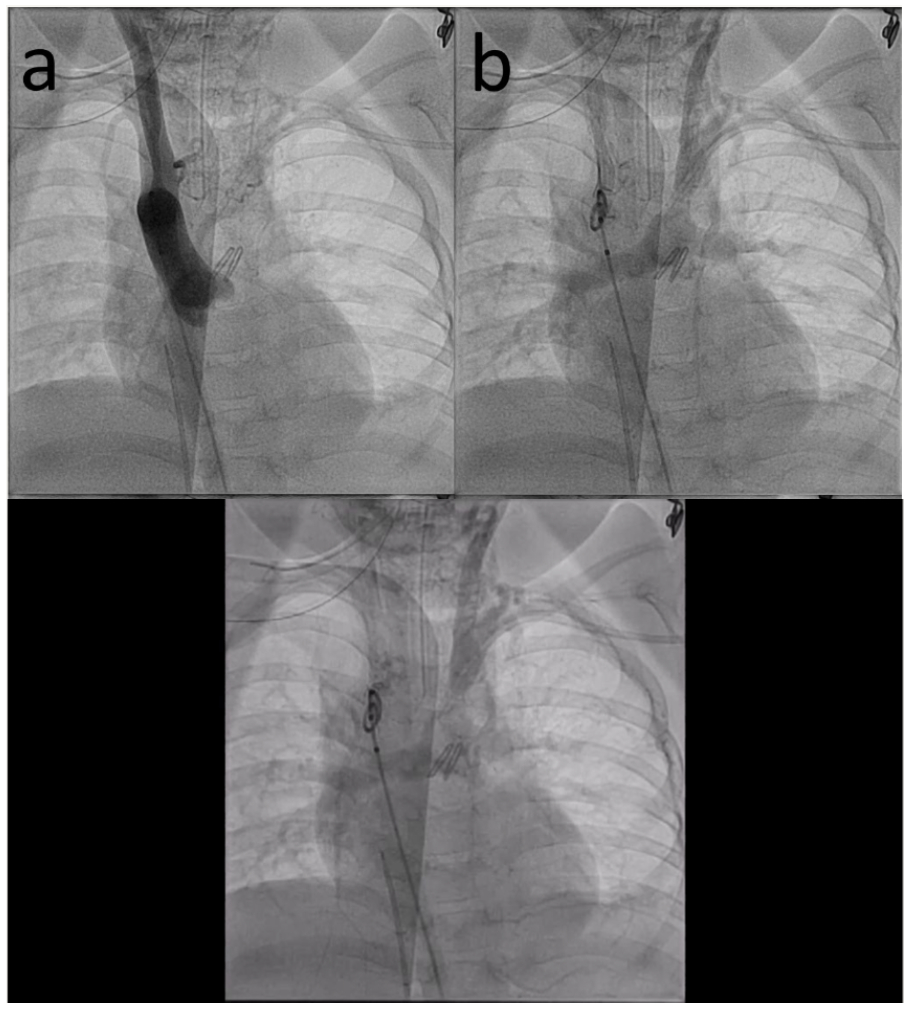

Aortic angiography showed a right aortic arch with only right carotid and right subclavian arteries and retrograde filling of the left carotid, left subclavian artery, and pulmonary arteries (Figure A/B, Video 1). Angiography of the left subclavian artery showed the tortuous, stenotic arterial connection between the pulmonary arteries and left subclavian artery (Figure C, Video 2). After stent placement, there was marked improvement in the caliber of the vessel and systemic saturations (Figure 1D, Video 3). Cerebral NIRS monitoring was used during the procedure with no change after stent placement. She has maintained reasonable saturations and has been seizure-free for over 3 years without neurologic deterioration or further cardiac intervention.